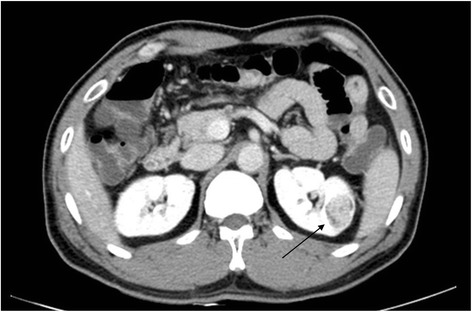

Case Report Case report of renal cell carcinoma in automobile manufacturing factory worker due to trichloroethylene exposure in Korea